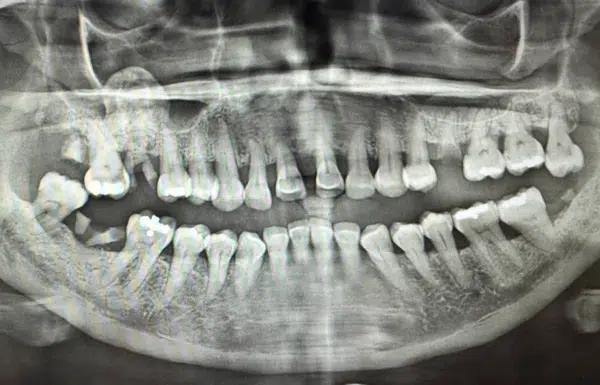

upper and lower All-on-4 dental implants

Before